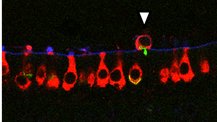

(11/14) Among these genes, a very robust response was found for a recently discovered gene specifically expressed in type I #haircells , Vsig10l2. This seems a good candidate as biomarker of #haircells stress.

(10/14) For several genes, we have been able to prove the reduced expression of the corresponding proteins

(9/14) The main result is the identification of 34 genes downregulated in all experimental conditions. Most (29) of these have been previously identified as specifically expressed in #haircells